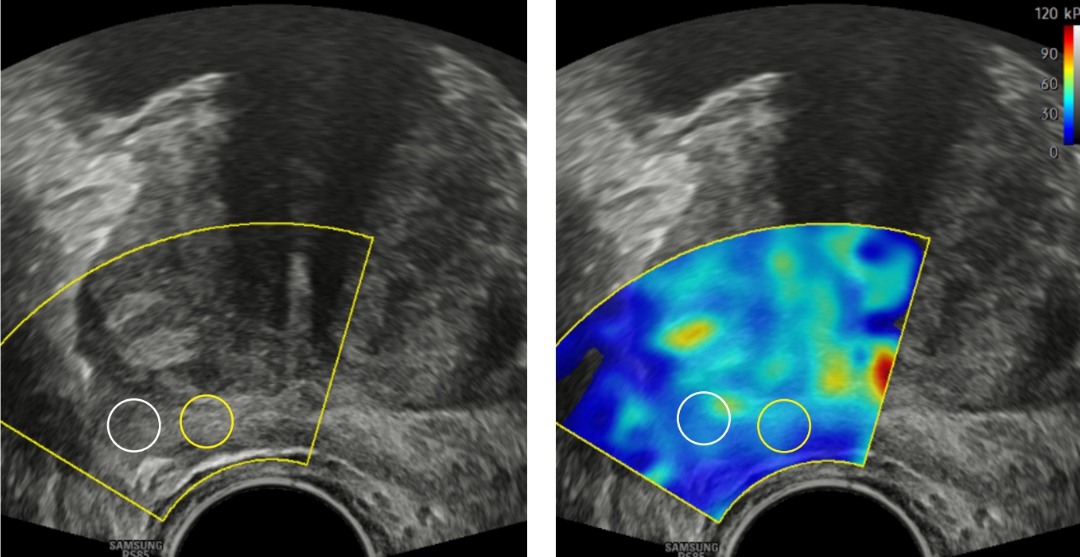

El método utiliza una molécula especial que se adhiere específicamente a las células del cáncer de próstata. Al realizar la tomografía por emisión de positrones (PET/CT) con PSMA, las células tumorales se iluminan y aparecen como puntos brillantes en la pantalla del médico.

El ensayo clínico demostró que el escaneo PET/CT con PSMA ofrece dos grandes ventajas:

- Identifica tumores agresivos: Detecta con precisión el cáncer de alto riesgo que sí requiere tratamiento inmediato.

- Frena el sobrediagnóstico: Detecta a pacientes sin cáncer o con tumores de tan bajo riesgo que no ameritan someterse a procedimientos invasivos ni a tratamientos innecesarios o perjudiciales.

En el caso de los pacientes que sí requirieron una biopsia, las imágenes sirvieron como un mapa exacto para que los médicos apuntaran directamente a las zonas sospechosas, mejorando la precisión y reduciendo las complicaciones.